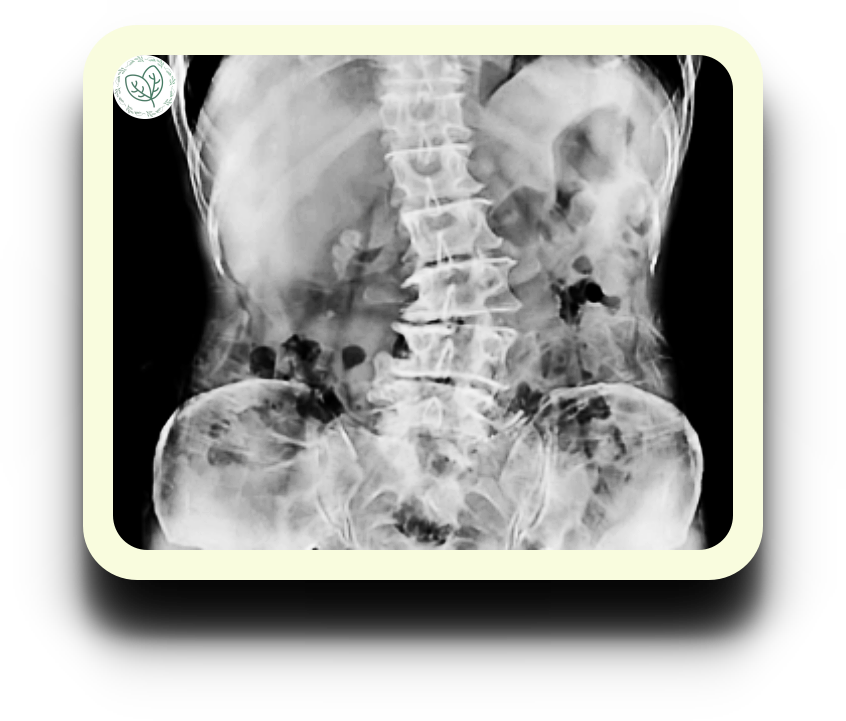

척추측만증에 대해 알아본 적 있나요? 척추가 옆으로 굽어져서 'S'나 'C' 모양을 이루는 상태를 가리키는 말입니다. 척추는 원래 앞뒤로 약간의 곡선을 가지고 있어요. 그래서 우리가 서 있을 때 머리가 몸의 중심에 위치하게 도와주죠. 그런데 이 척추가 옆으로 곡선을 그리며 휘는 건 문제입니다. 이런 상태는 X-레이로 확인할 수 있으며, 한쪽 어깨가 다른 쪽보다 높아지거나 허리 한쪽이 들어가는 등의 외관적인 변화를 통해 확인할 수 있어요.